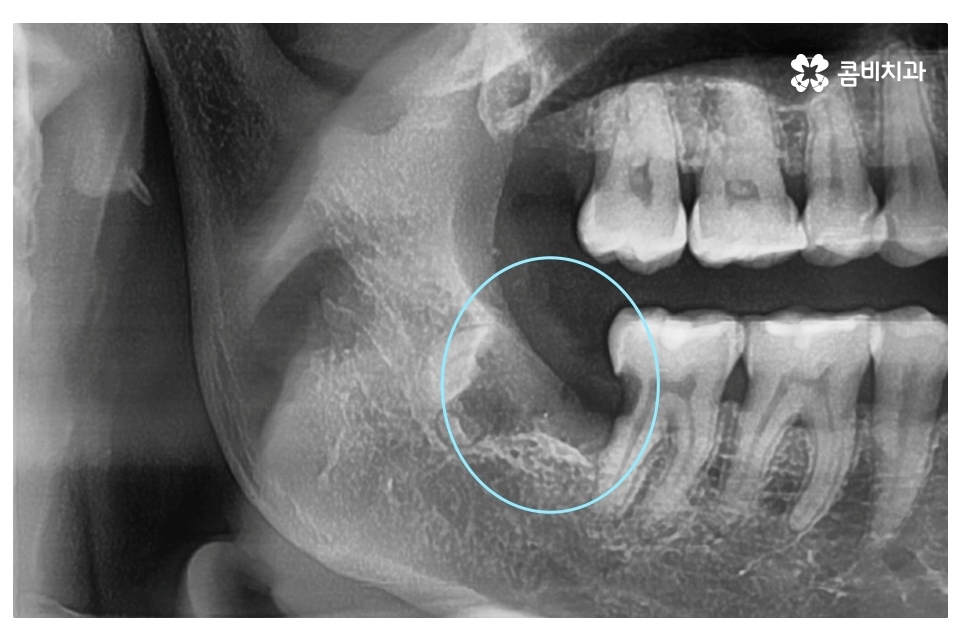

대표적으로 발치를 해야 하는 케이스는 사랑니가

누워서 자라면서 어금니 혹은 잇몸에 안 좋은 영향을

주는 경우이며 사랑니에 충치가 발생한 경우,

잇몸에 염증을 유발하는 경우 등이 있어요.

사랑니가 누워서 자라는 경우에 어금니 사이에 음식물이 끼기 쉽고

오늘 보여드린 환자분의 케이스는 사랑니로 인해 어금니에도

충치가 발생한 사례로 이처럼 치아 사이에 충치가 발생하면

치아의 하단부, 안쪽에 손상이 발생하기 때문에

어금니 신경치료를 하게 되는 경우로 이어질 수 있어요.

위처럼 누운 사랑니의 경우 단지 사랑니의 발치 만으로 끝나는 것이 아니라

주변 치아, 평생 지켜야 할 어금니 손상을 유발할 수 있기 때문에

엑스레이 사진에서 보시는 것처럼 사랑니로 인해 어금니 옆 부분에

충치가 발생되었고 사랑니 발치 후 어금니 신경치료를 하여

자연치아의 손상이 커진 케이스라고 할 수 있는데요